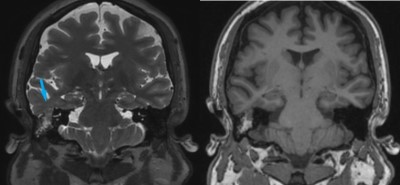

This is a 28 year old female who presents with complaint of right-sided hearing loss and sense of fullness within her right ear.

Her exam is consistent with conductive hearing loss in right ear.